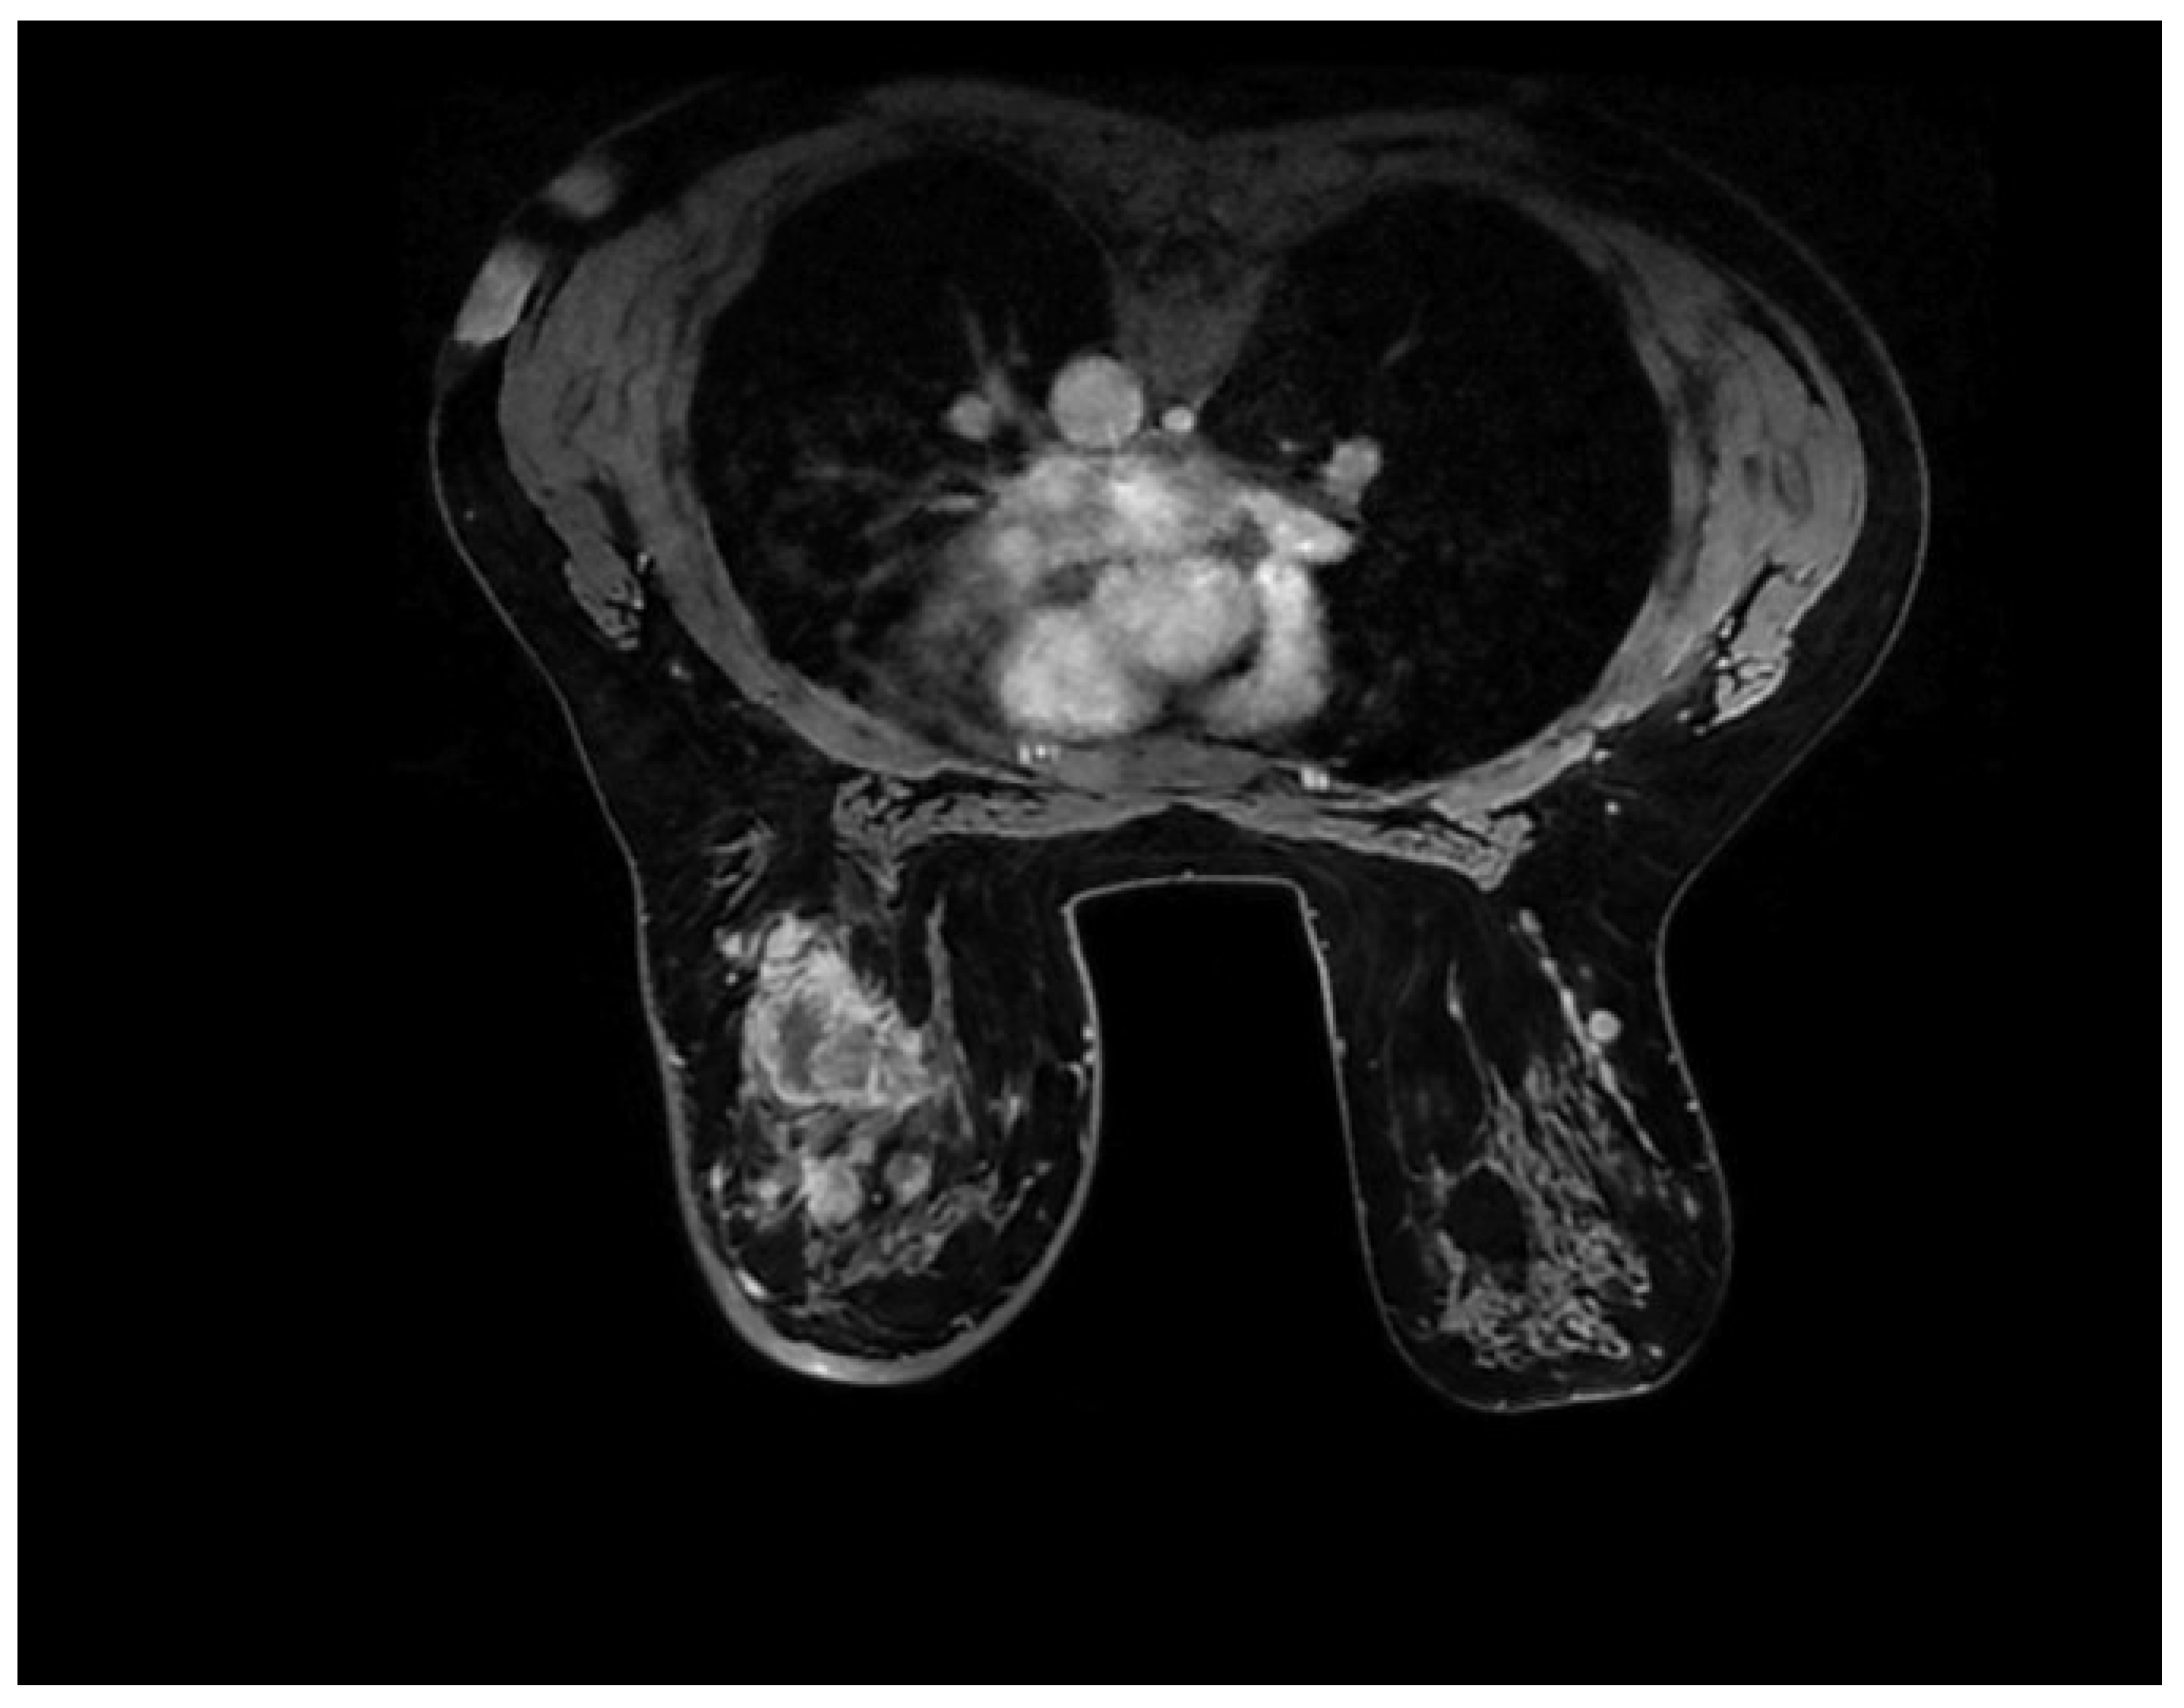

2.4. Magnetic Resonance Imaging (MRI)

3.7. Correlations between Molecular Subtypes of BC and Their Features on MRI

- Szep, M.; Pintican, R.; Boca, B.; Perja, A.; Duma, M.; Feier, D.; Fetica, B.; Eniu, D.; Dudea, S.M.; Chiorean, A. Multiparametric MRI Features of Breast Cancer Molecular Subtypes. Medicina 2022, 58, 1716. [Google Scholar] [CrossRef] [PubMed]

- Öztürk, V.S.; Polat, Y.D.; Soyder, A.; Tanyeri, A.; Karaman, C.Z.; Taşkın, F. The Relationship Between MRI Findings and Molecular Subtypes in Women With Breast Cancer. Curr. Probl. Diagn. Radiol. 2020, 49, 417–421. [Google Scholar] [CrossRef]

- Ab Mumin, N.; Ramli Hamid, M.T.; Wong, J.H.D.; Rahmat, K.; Ng, K.H. Magnetic Resonance Imaging Phenotypes of Breast Cancer Molecular Subtypes: A Systematic Review. Acad. Radiol. 2022, 29, S89–S106. [Google Scholar] [CrossRef] [PubMed]